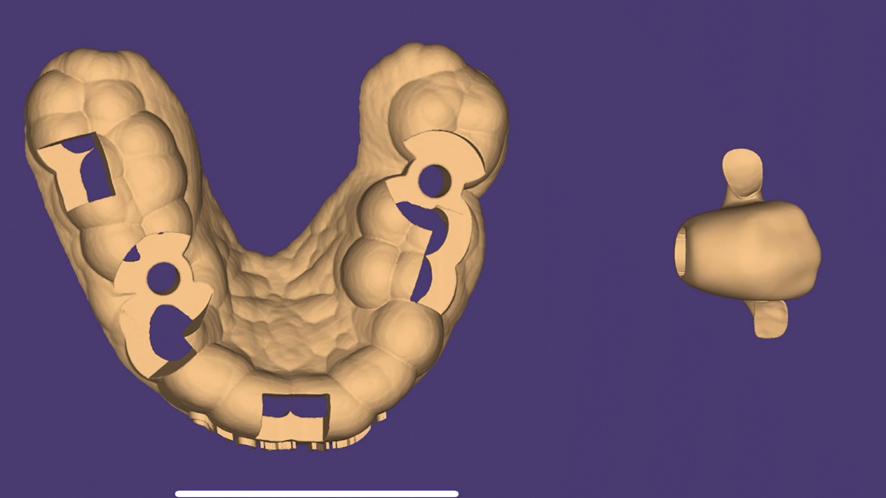

Com o correto planejamento digital através da tomográfica computadorizada e um escaneamento digital da região, a técnica da cirurgia guiada surge com um procedimento previsível (DAL PIVA et al., 2018). O guia cirúrgico propriamente dito é obtido a partir do planejamento virtual, onde já foi definido pelo implantodontista o número de implantes e onde eles serão instalados, transferindo o planejamento virtual para o real através da guia impressa.7,11

Para o planejamento reverso foi realizado escaneamento digital e obtido o modelo digital da boca do paciente, assim como também a tomografia Cone Beam da regão para a confecção do guia cirúrgico. Foi planejando também a necessidade de realizar enxerto ósseo do tipo heterogêneo com colágeno para o preenchimento do GAP da região, visando assim criar um bom perfil de emergência e reduzir a chance de perda volumétrica. Foi planejado também um provisório de PMMA a partir de software de planejamento e enceramento digital 3D (Exocad).

Após a exodontia foi posicionado o guia cirúrgico impresso e iniciou-se o protocolo de fresagem do kit cirúrgico Implaguide da Implacil De Bortoli: fresa lança 2,0, seguida pela fresa 3,5×13, buscando subfresagem para maior estabilidade primária. O implante dentário instalado foi o Maestro de 4x13mm (Implacil De Bortoli). Foi realizado em seguida a instalação do pilar Ideale 4,5 x 4 x 2,5 mm e a coifa parafusada do pilar Ideale 4,5x4mm.